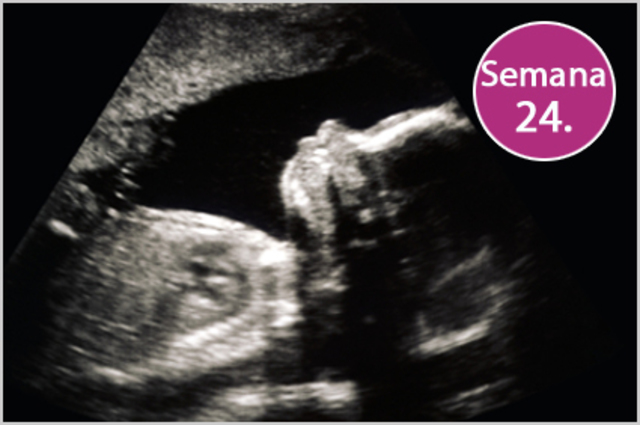

• Semana 24

Semana 24

-El feto recibe primeros estímulos del mundo exterior.